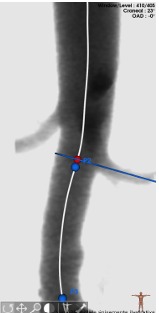

Afortunadamente, Sonora se consolida como un referente en atención médica al ofrecer tratamientos innovadores de vanguardia, como un procedimiento quirúrgico denominado Reparación Endovascular de Aneurisma Aórtico Abdominal (EVAR), técnica mínimamente invasiva consistente en la realización de pequeñas incisiones en la ingle para introducir un catéter hasta llegar al aneurisma y cubrirlo con un stent-injerto de alta tecnología, conocido como prótesis Aorfix, capaz de fortalecer la pared arterial, reduciendo el riesgo de ruptura y sangrado, ofreciendo así una solución eficaz y segura para quienes enfrentan esta condición de salud.

La prótesis Aorfix es un dispositivo médico diseñado para el tratamiento de aneurismas de la aorta abdominal, especialmente en pacientes de alto riesgo con anatomías complejas, como aortas tortuosas o con angulaciones, donde otras endoprótesis podrían no adaptarse correctamente, y cuyo diseño flexible minimiza el riesgo de complicaciones durante su colocación, además de promover una recuperación más rápida en los pacientes.